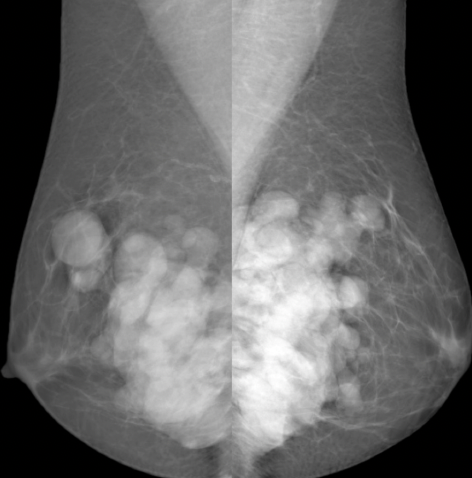

multiple round masses of varying size in both breasts. masses are very well defined, have a black halo (benign appearance on mammography)

Appearance in keeping with cysts however requires an ultrasound to make a definitive diagnosis